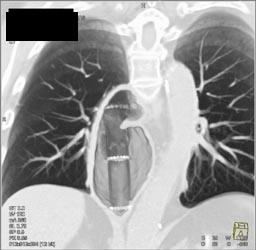

Increased Pulmonary Blood Flow to Lower Lung Fields